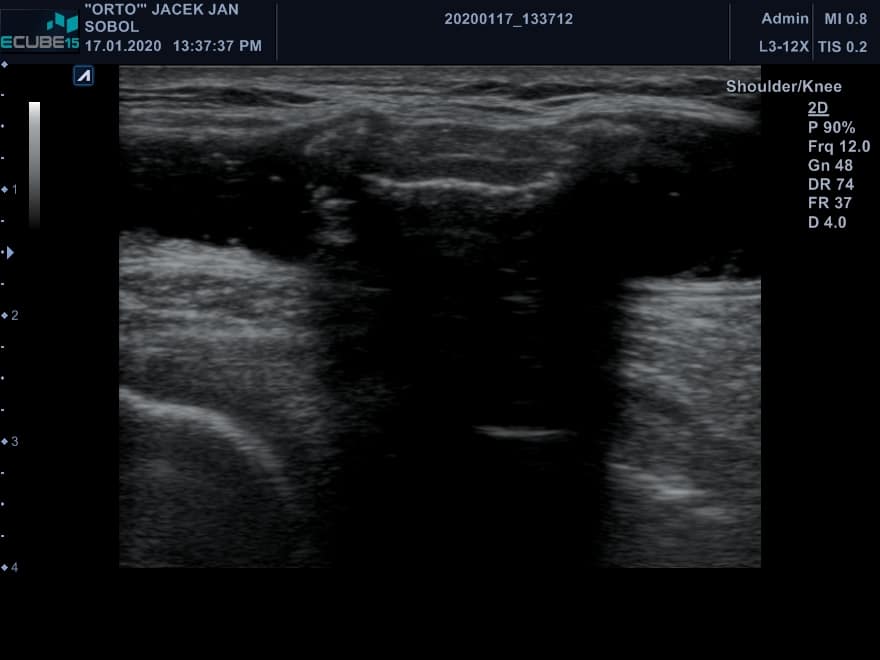

Przypadek pacjenta z dużą torbielą dołu podkolanowego. W obrębie torbieli widoczne duże cieniujące ciało wolne. Na ilustracji nr. 2 dodatkowo widoczna igła – punkcja torbieli, sprawdzenie mobilności ciała wolnego. Widoczny również tylny obrys kości udowej i piszczelowej. Torbiel dołu podkolanowego dobrze wypełniona, na długości całego obszaru obrazowania. Ciało wolne pochodzi najprawdopodobniej z jamy stawu kolanowego. Przypuszczalnie jest to fragment chrzęstno-kostny. Można je usunąć operacyjnie w trakcie artroskopii kolana.